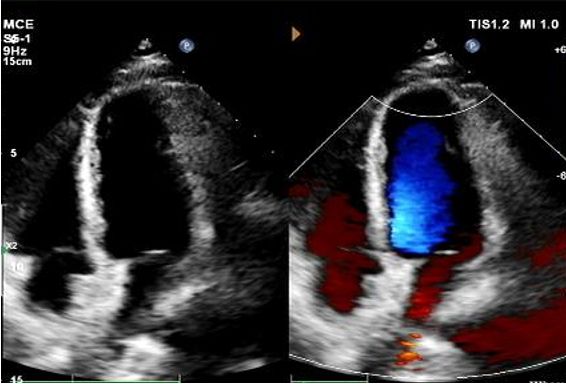

1-Year Echo:

No visible disc structures – replaced by 8mm tissue thickening at the septal implant site.

Zero residual shunt (rest or post-Valsalva).

Complete device absorption confirmed.